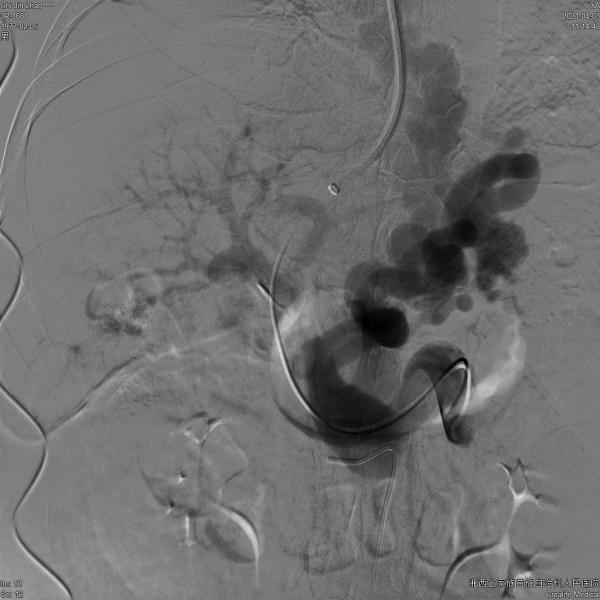

4月3日,介入科团队成功完成湘西州首例自主TIPS手术,手术建立了肝内门腔静脉通道,明显降低了门静脉压力,完全封闭了明显曲张的食管胃底静脉。

▲术前造影:巨大的胃底食管静脉曲张

▲术后造影:粗大的曲张静脉消失,支架内血流通畅